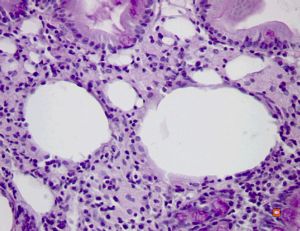

cured Whipple disease (HE)